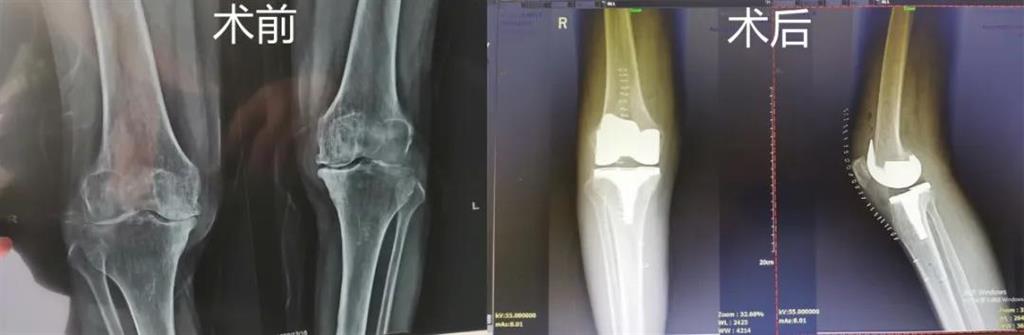

計(jì)算機(jī)導(dǎo)航膝關(guān)節(jié)置換術(shù)過程部分畫面